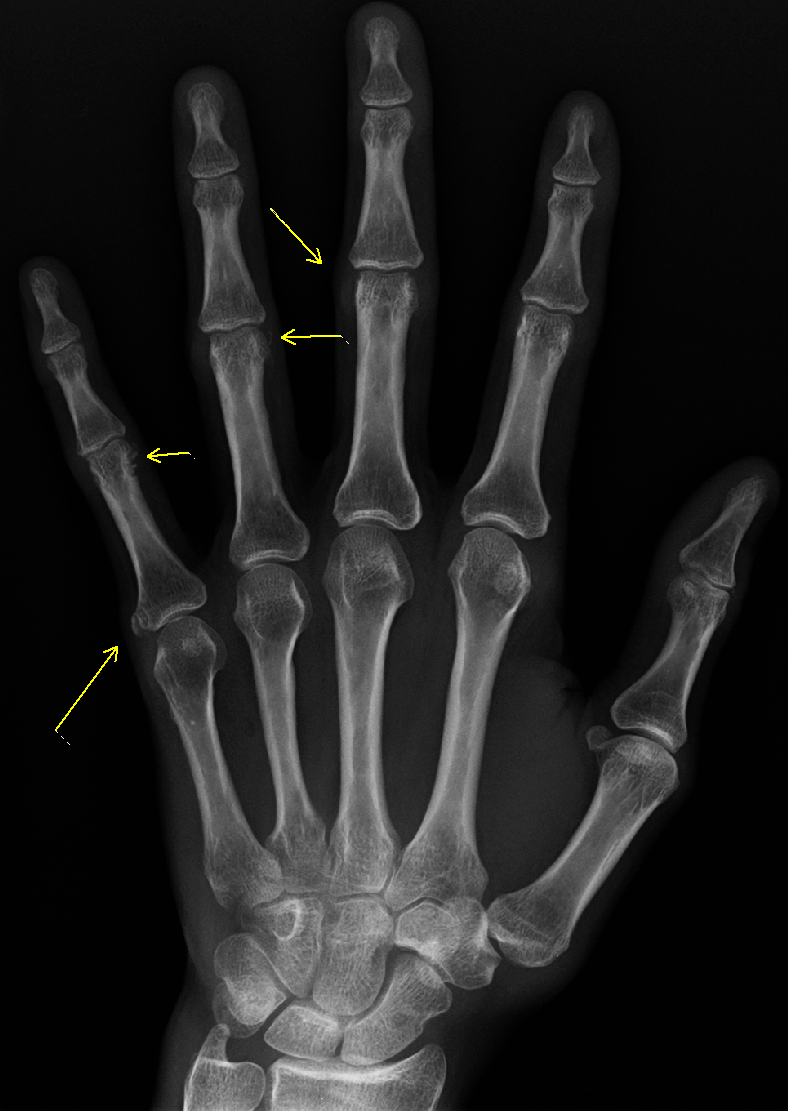

CREST 증후군 (석회증과 손발가락경화증)

CREST 증후군(석회증 및 경화지증)

CREST 증후군 환자의 석회증을 보여주는 X-레이

• Calcinosis(석회증): 피부가 두꺼워지고 팽팽해지며 칼슘 침착 결절이 생긴다.

2. 1. 석회증 (Calcinosis)

피부가 두꺼워지고 팽팽해지며 칼슘 침착 결절(Calcinosis|칼시노시스영어)이 생긴다.[1]